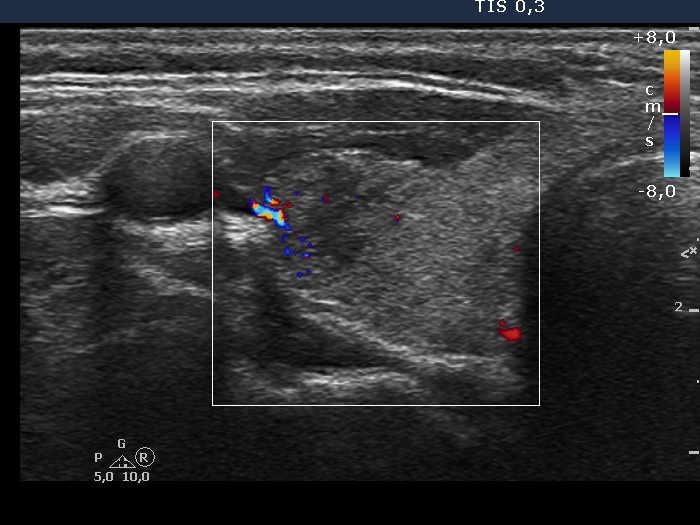

Ultrasonography: The thyroid was minimally hypoechogenic and contained multiple small hypoechogenic areas with sharp, puzzle-like borders. The vascularization was a little bit increased.

Cytology: The largest hypoechogenic lesion in the ventromedial part of the left lobe was aspirated. The cytological pattern was consistent with thyroiditis.